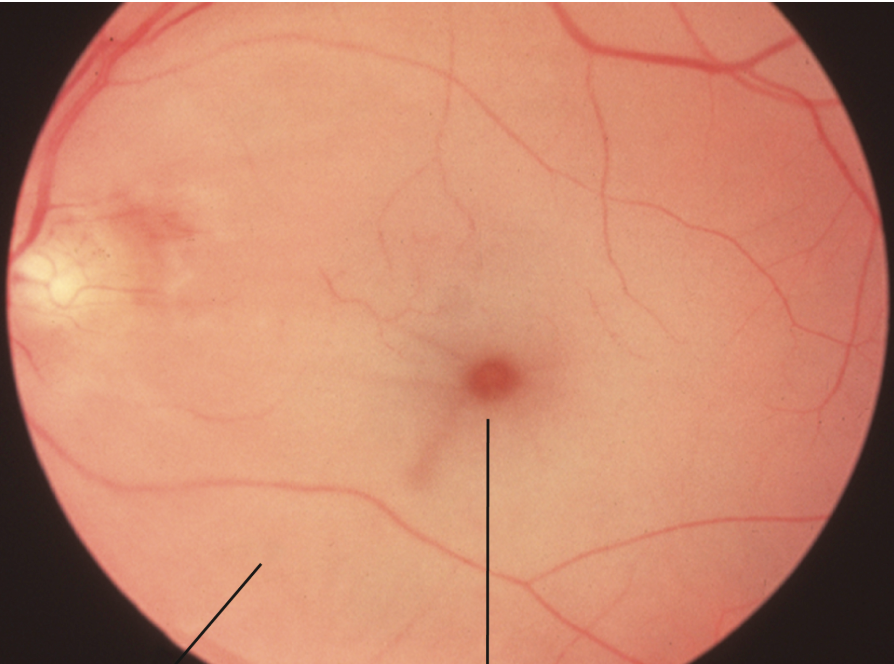

Diagnosis?

A

Acute central retinal artery occlusion

• pale and edematous retina

• cherry red spot

• retinal veins intact